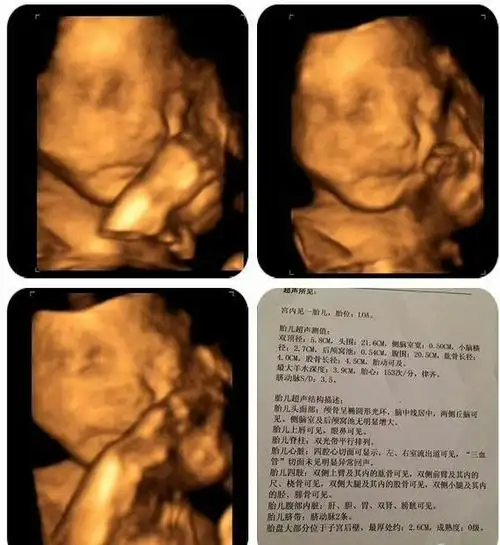

双胎宝妈21周做四维彩超筛查出一名胎儿为唇腭裂

双胎宝妈21周做四维彩超,筛查出一名胎儿为"唇腭裂"